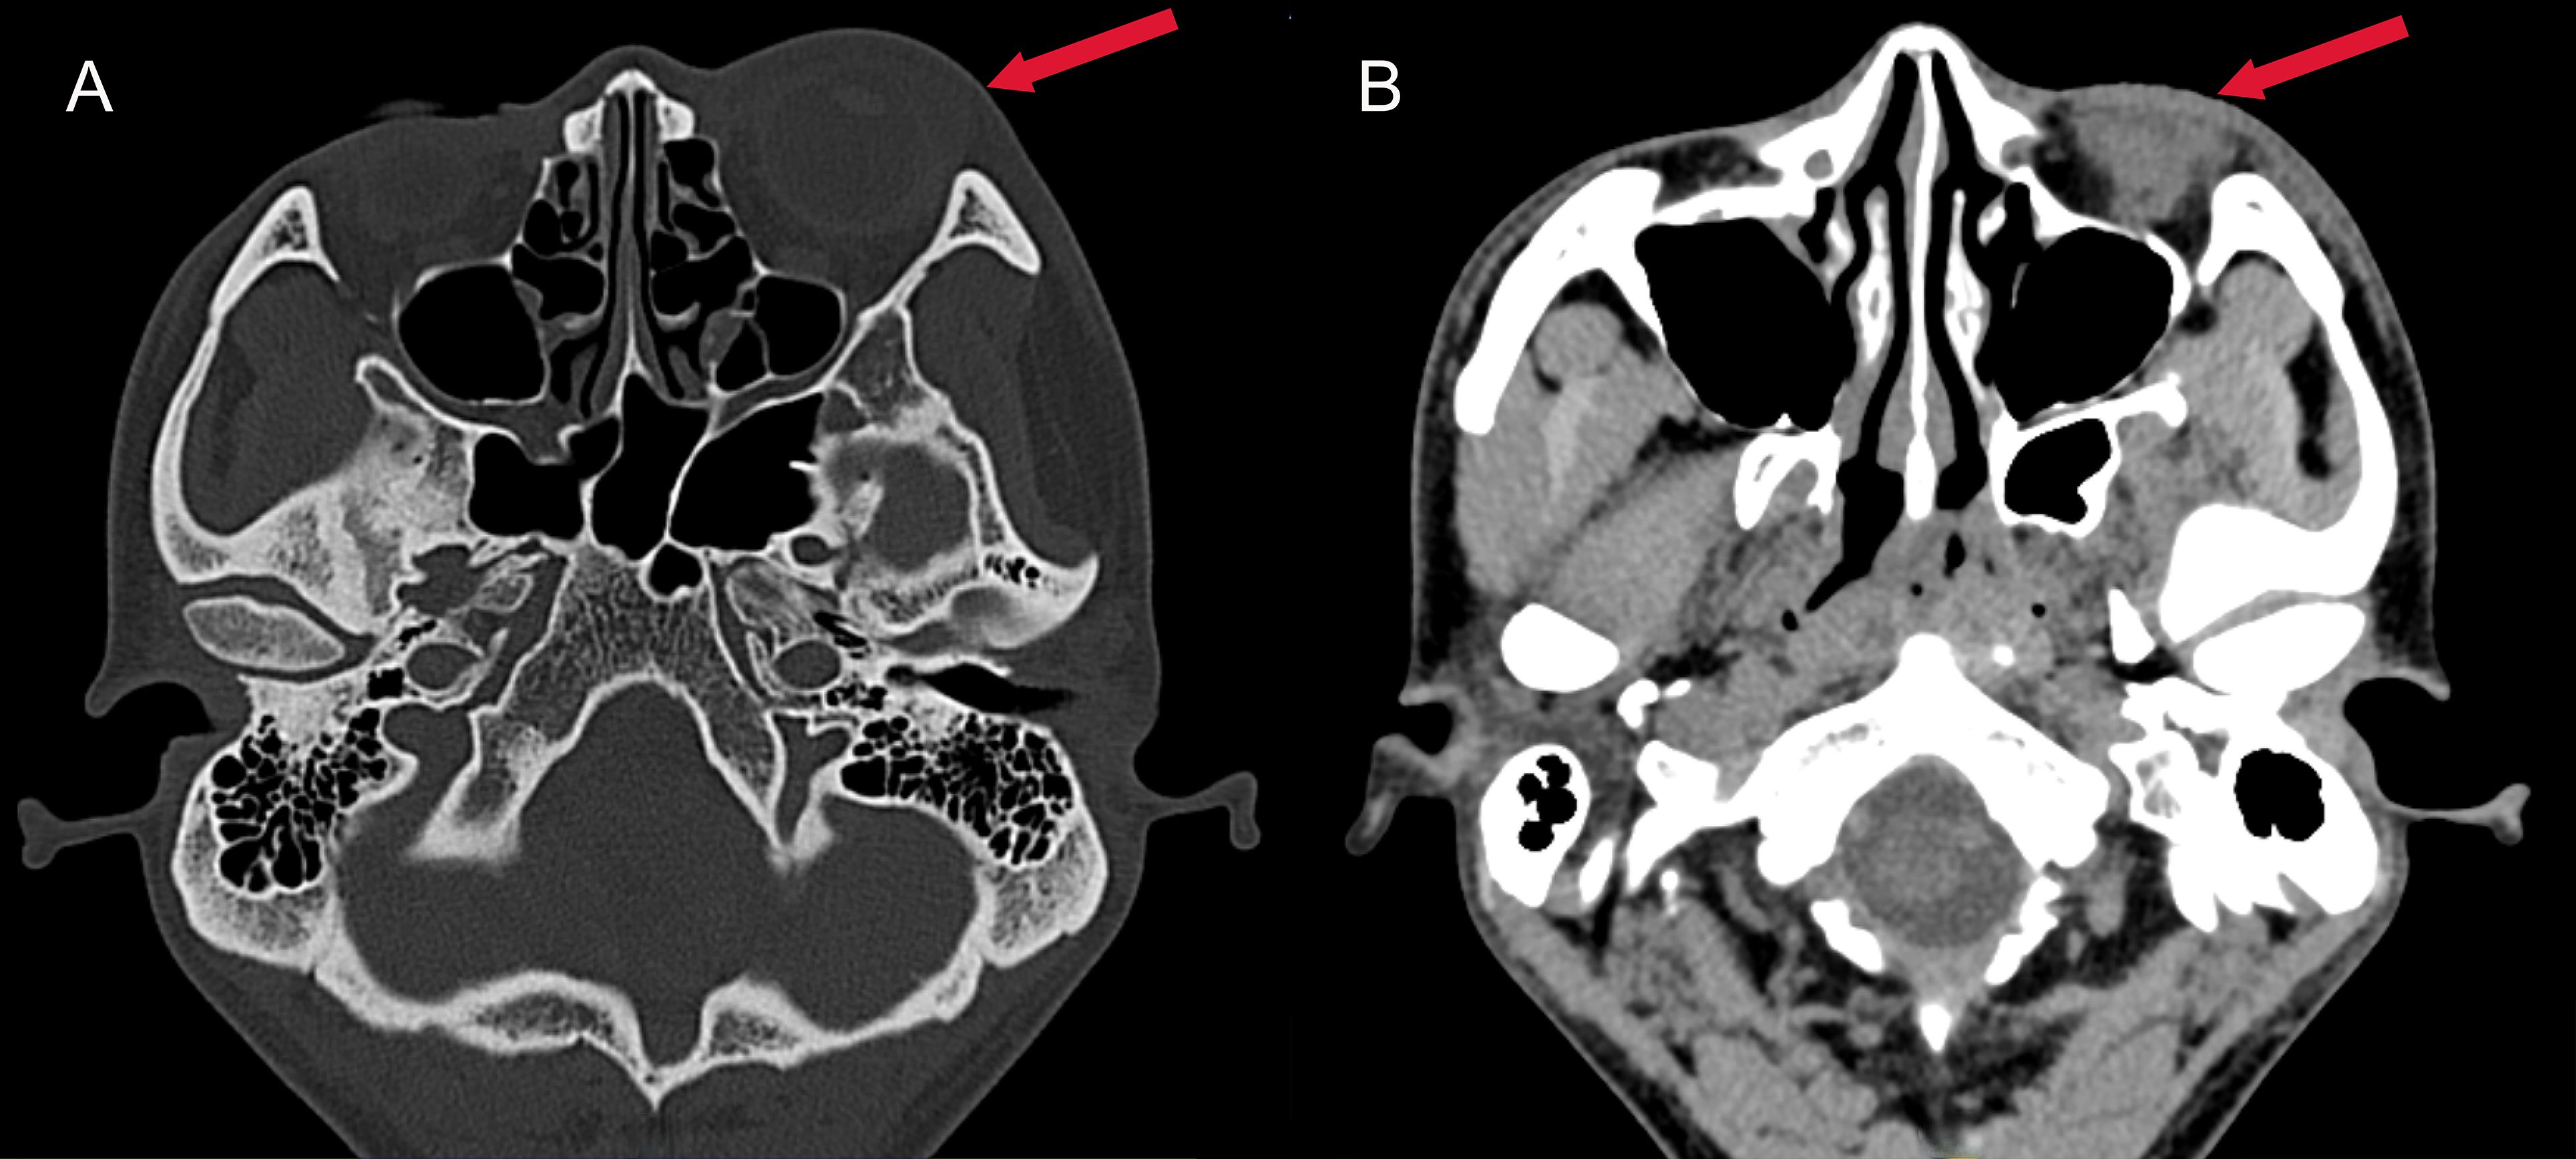

A previously healthy 25-year-old male developed high fever (maximum 40°C) without an identifiable cause while traveling in Jiangxi, China. The fever was accompanied by mild cough and sputum production. Despite self-medicating with over-the-counter cold medication, his symptoms persisted. Five days later, he experienced sudden onset of blurred vision, redness, and painful swelling in his left eye. After nearly a week of persistent symptoms without improvement, he underwent a chest CT scan, which revealed a pulmonary mass, prompting further evaluation. Upon hospital admission on August 2, 2024, CT imaging demonstrated multiple pulmonary nodules with partial cavitation, suggesting a possible infectious etiology (Figure 1). Orbital CT revealed an intraocular mass in the left eye, with irregular margins of the left globe and heterogeneous attenuation in the peribulbar and orbital apex tissues (Figure 2). Additionally, a low-density hepatic lesion was identified (Figure 3), raising suspicion of a liver abscess, and a low-density nodule was detected in the right thyroid lobe. Laboratory tests revealed leukocytosis and significantly elevated inflammatory markers, leading to the initiation of empiric antibiotic therapy with ceftriaxone sodium. Two sets of peripheral blood cultures collected on August 4, 2024 (left and right upper limbs) were negative; blood cultures were not repeated. Due to patient non-cooperation, a complete ophthalmologic evaluation of the left eye was not feasible. Hemodynamics remained stable without vasopressors (SBP 110–130 mmHg/DBP 70–85 mmHg); lactate was 1.2 mmol/L, urine output was ≥1 mL/kg/h, and mental status was normal, indicating no clinical evidence of septic shock. On August 5, 2024, bronchoalveolar lavage fluid (BALF) culture grew K. pneumoniae without detected antimicrobial resistance. Metagenomic next-generation sequencing (mNGS) of bronchoalveolar lavage (BAL) fluid further confirmed the presence of K. pneumoniae. Given the severity of the infection, the antimicrobial regimen was escalated to meropenem. Despite intensive antimicrobial therapy, the infection progressed rapidly, affecting multiple organ systems. The patient was diagnosed with invasive K. pneumoniae syndrome, characterized by pulmonary abscess, liver abscess, thyroid nodule, and endogenous endophthalmitis with retinal detachment. Given the disseminated nature of the infection, the antimicrobial regimen was further adjusted to meropenem plus levofloxacin. Although systemic infection was gradually controlled, the left eye infection continued to deteriorate. The patient developed worsening ocular pain and progressive vision loss. Ophthalmologic evaluation revealed scleral ulcer perforation with extensive orbital tissue necrosis, resulting in irreversible ocular damage. Due to the severity of the infection, on August 21, 2024, the patient underwent left ocular enucleation. Postoperative ocular tissue cultures confirmed K. pneumoniae infection. Following surgery, the antimicrobial regimen was adjusted from meropenem plus levofloxacin to cefoperazone-sulbactam. By the time of discharge, follow-up imaging demonstrated a reduction in pulmonary and hepatic abscess size, with adequate infection control. Figure 4 illustrates the detailed course of disease progression.

Figure 2. Axial CT images of the head. (A) Bone window CT revealing swelling of the left eye (red arrow); (B) Contrast-enhanced soft tissue window showing exudation in the left eye (red arrow), characterized by a hypodense area in the periorbital soft tissues.